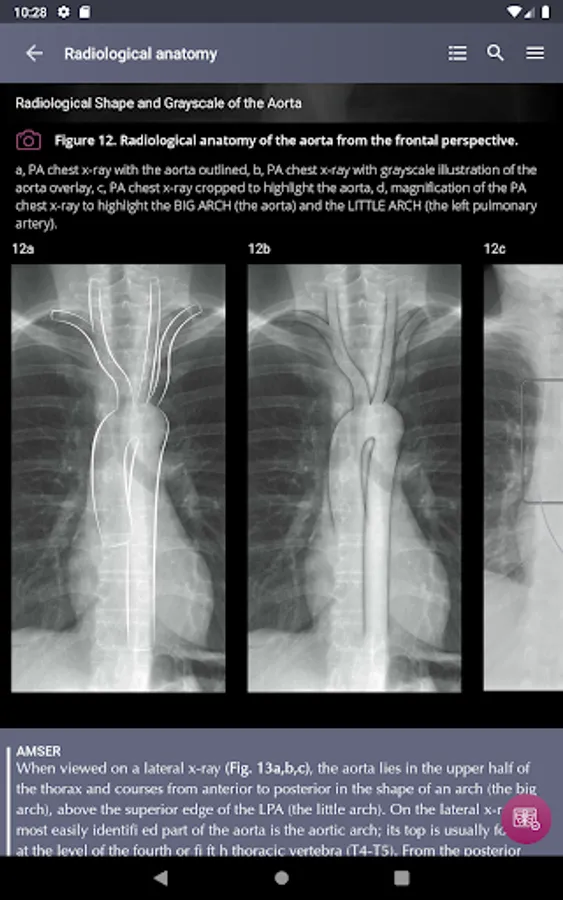

Section II* introduces the concept of radiological zones to give you a starting point in the understanding of the radiological anatomy of the chest. The next chapters review in detail the radiological anatomy of specific anatomical structures, also provide examples of how the x-ray image can change due to pathology. The final chapter explains how the individual structures come together to form the radiological image.

Radiological Anatomy – Descriptions of various anatomical structures as they would appear on PA and lateral chest x-rays.